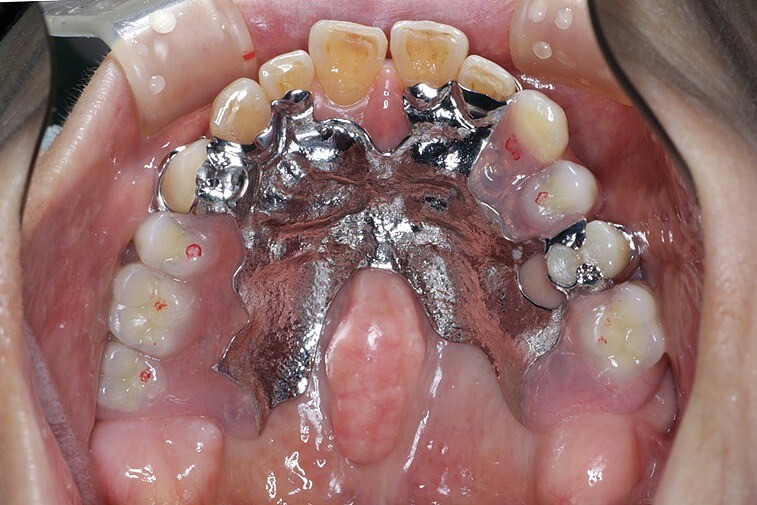

63歳男性

こちらは、「保険の入れ歯が合わず、食事がおいしく感じられない」とのことで来院された患者さまです。

上顎に金属床義歯を新たに製作し、入れ歯がしっかり合うように設計しました。ちょっとした形態の工夫が、装着時の快適さにつながる大きなポイントとなります。

金属床義歯の分野で著名な技工士による製作により、薄くてフィット感の高い入れ歯が完成しました。装着後は「しっかり噛めるようになった」と、患者さまにも大変ご満足いただけました。

| 主訴 | 保険の入れ歯が合わない。食事が美味しくない。 |

| 治療内容 | 上顎金属床義歯 |

| 治療期間 | 6ヶ月 |

| 治療費 | 約1,500,000円 |

| リスク・副作用 | ※予後を完全に保証する治療ではありません。※自由診療での治療です。※精密な装置であるため装置が落としたときに破損する時があります。 |